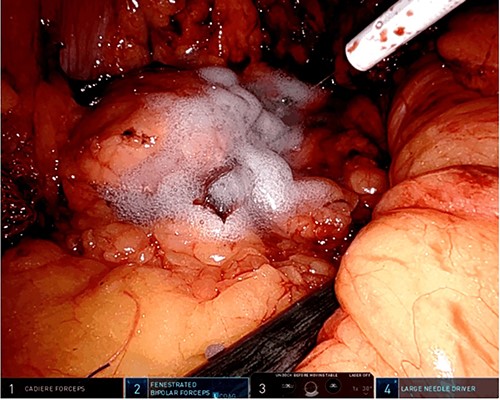

A robotic redo distal pancreatectomy was performed. Adhesions from the previous operation were taken down and the pancreatic stump was dissected. Samples of lymphatic tissue were sent for permanent pathology. An intraoperative ultrasound scan was done to localize the tumor and rule out concomitant lesions. A 2-cm nodule was found in the pancreatic stump (Fig. 3). With precise dissection, the gland was mobilized, reaching the confluence of the splenic and the portal vein. Afterward, the pancreatic stump was resected using a linear stapler (Fig. 4A and B). Once hemostasis was obtained, fibrin glue was applied to the section line and two drains were left close to the stump (Fig. 5). The patient was discharged on postoperative day 7. She developed a pancreatic biochemical leak that was managed conservatively. The histopathology analysis showed a grade 2, 1.3 cm well-differentiated neuroendocrine tumor with a low mitotic rate and Ki 67 index of 3%. After 16 months of follow-up, there was no evidence of recurrence.

Intraoperative ultrasound revealing a 2 cm lesion in the pancreatic stump.